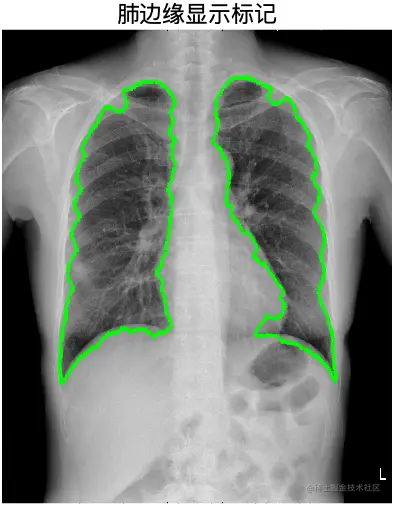

运行结果

image.png

% 提取肺边缘

ed = bwboundaries(bw_temp);

% 显示

figure;

subplot(2, 2, 1); imshow(I, []); title('原图像');

subplot(2, 2, 2); imshow(J, []); title('增强图像');

subplot(2, 2, 3); imshow(bw_temp, []); title('二值化图像');

subplot(2, 2, 4); imshow(I, []); hold on;

for k = 1 : length(ed)

% 边缘

boundary = ed{k};

plot(boundary(:,2), boundary(:,1), 'g', 'LineWidth', 2);

end

title('肺边缘显示标记');